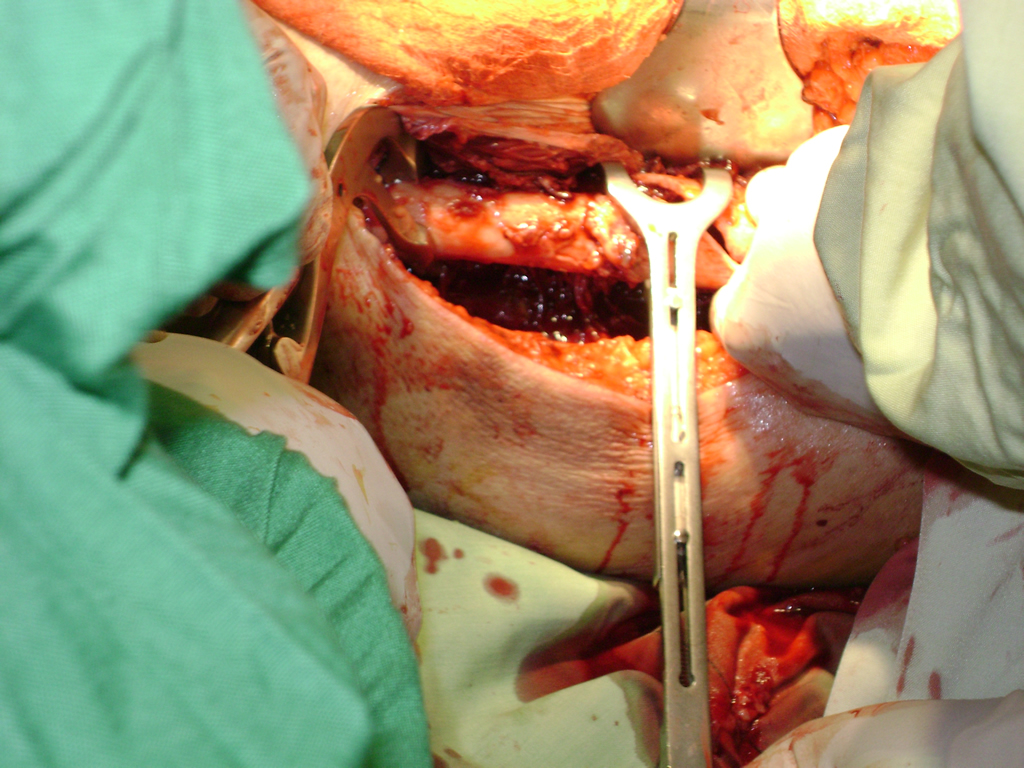

Cirugía de Fémur - Cadera

La cirugía de fractura de cadera se realiza para reparar una ruptura en la parte superior del hueso del muslo. Este hueso se denomina fémur.